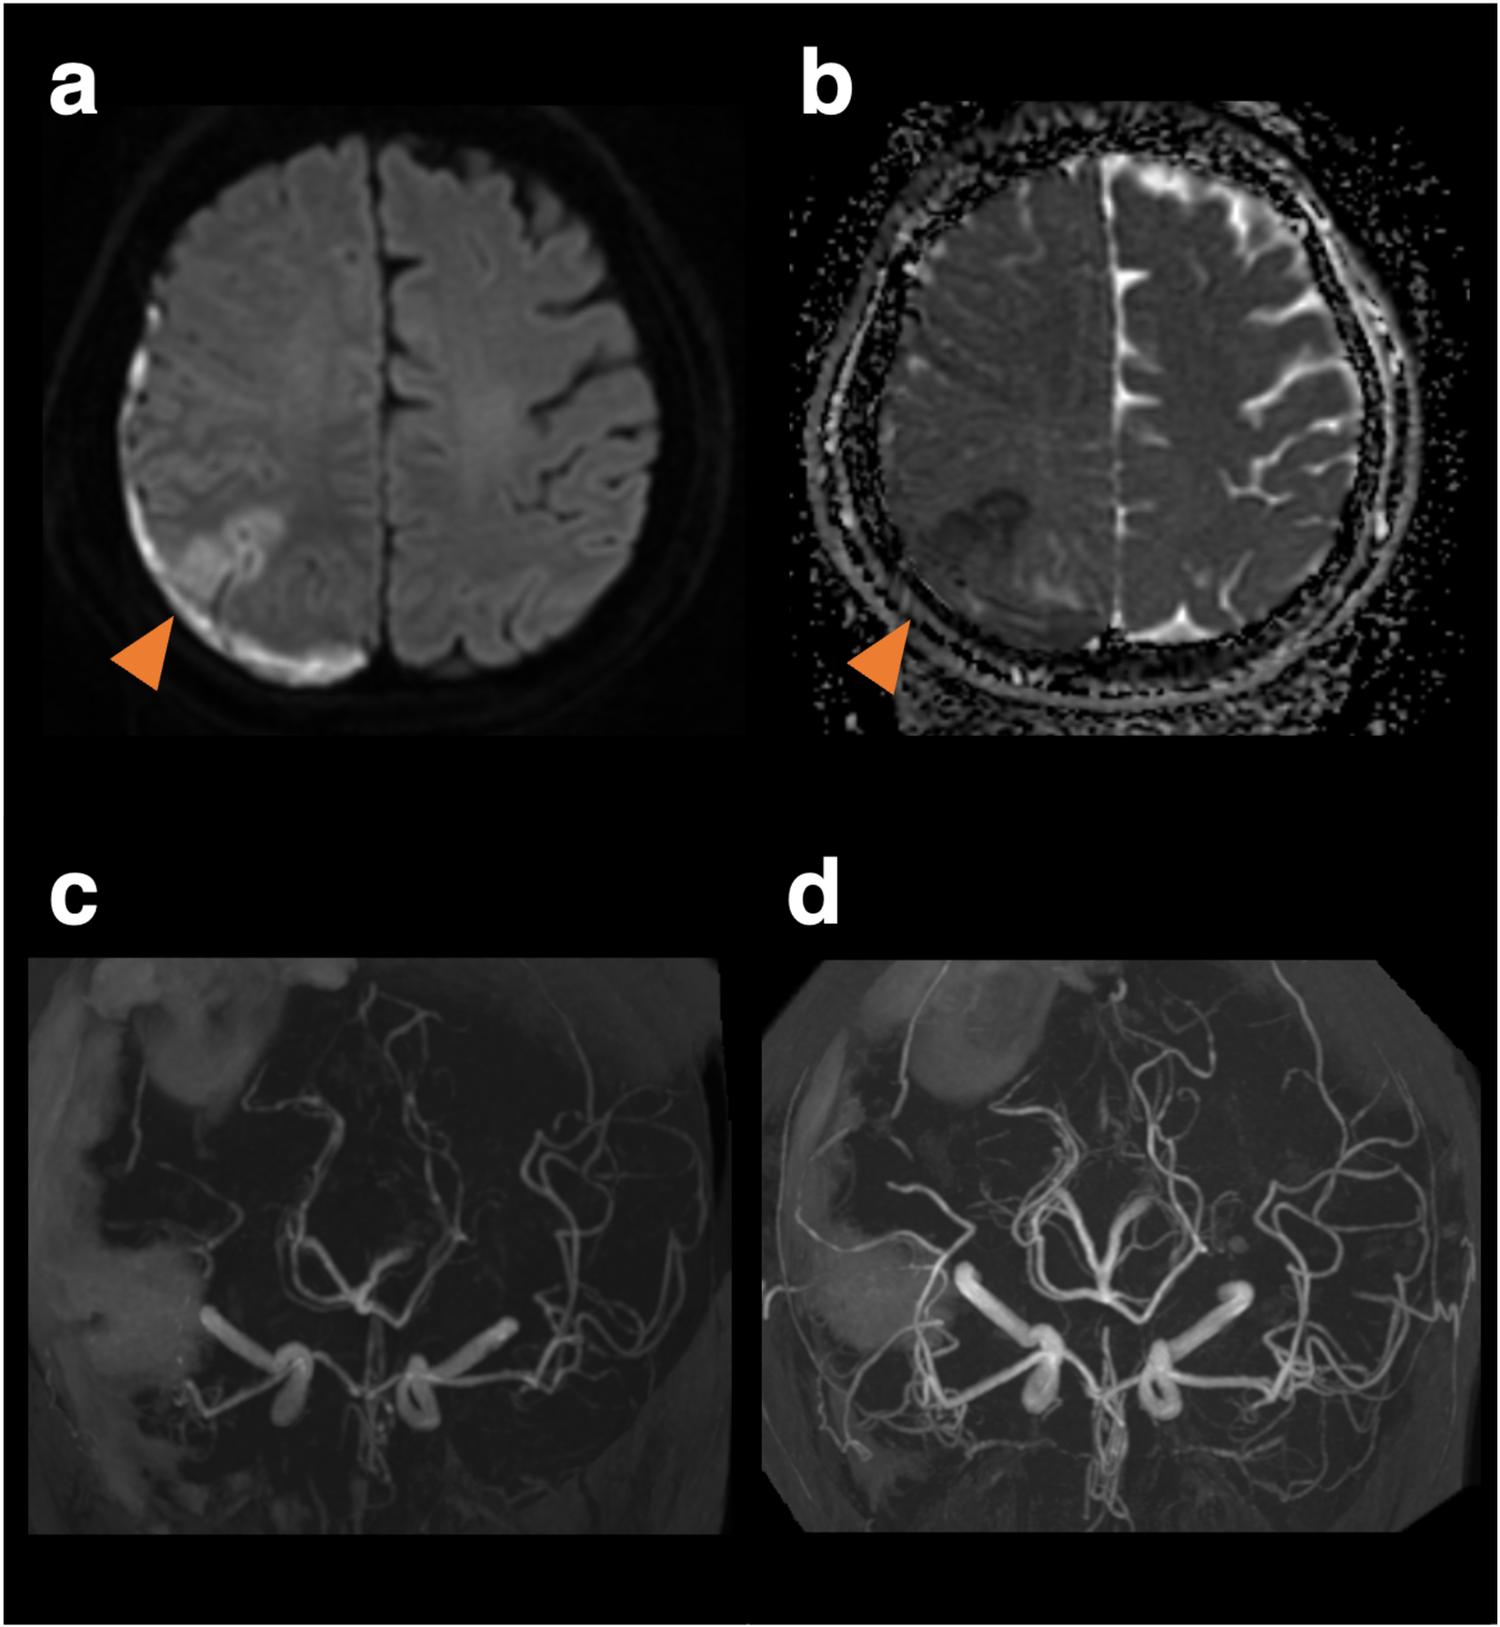

A 59-year-old woman with cardiomyopathy due to Duchenne muscular dystrophy underwent cardiac transplantation. Her pre-transplant history included muscular dystrophy-related weakness but no history of hypertension, migraine, or other significant cardiovascular comorbidities. Her perioperative immunosuppression regimen consisted of tacrolimus, mycophenolate mofetil, and prednisolone. She had been taking aspirin for donor-transmitted coronary atherosclerosis. Her postoperative course was complicated by labile hypertension, with systolic pressures ranging from 140 to 180 mmHg. On day nine, she developed a headache. Neurological examination revealed left lower quadrantanopia. A head Computed Tomography (CT) scan showed a subdural hematoma with a maximum thickness of 1 cm, along with a subcortical and convexity subarachnoid hemorrhage in the right parieto-occipital lobe (Figures 1a,b). CT angiography revealed stenosis confined to the left middle cerebral artery, though it was unclear whether this represented vasospasm or mere stenosis (Figures 1c,d). MR imaging was not immediately available due to the presence of transplant-related devices. Discontinuation of aspirin did not prevent the development of left hemineglect on the 10th day. After the transplant-related devices were removed, cranial MR images on the 10th day revealed a watershed infarct in the right parietal lobe (Figures 2a,b), and MR angiography demonstrated diffuse, multifocal moderate vasospasms affecting the bilateral anterior, middle, and posterior cerebral arteries (Figure 2c). She was diagnosed with RCVS. Management included immediate withdrawal of tacrolimus and initiation of oral verapamil. Following the identification of the watershed infarct, an antiplatelet agent was considered for secondary stroke prevention. Prasugrel was chosen over other P2Y12 inhibitors because its antiplatelet effect is not influenced by CYP2C19 loss-of-function variants, which are prevalent in Asian populations (5). This regimen led to an improvement in her neurologic symptoms within 24 h, and follow-up MR angiography on day 18 showed improvement in the vasospasm (Figure 2d). Her immunosuppressive regimen was adjusted to a combination of prednisolone, everolimus, and mycophenolate mofetil, and then gradually tapered. She was discharged home on day 49. At a 6-month follow-up visit, she remained neurologically stable with a persistent, isolated left lower quadrantanopia but was independent in her activities of daily living (modified Rankin Scale score of 1). Follow-up cranial magnetic resonance imaging at 6 months revealed no new infarction or hemorrhage and no recurrence of vasospasm.

Figure 2

Magnetic resonance images and angiography on the 10th day when the patient developed left hemineglect, and magnetic resonance angiography on the 18th day of follow-up. Diffusion-weighted imaging (a) and apparent diffusion coefficient map (b) reveals a watershed infarct. Vasoconstriction peaked on day 10 (c) and improved on day 18 (d).